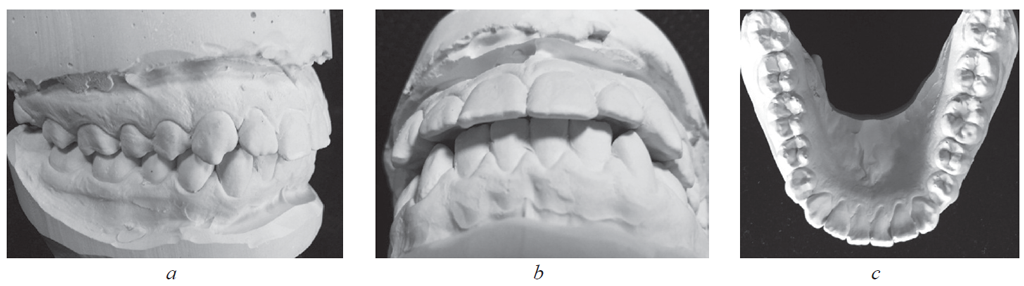

У пациентов 1-й группы с физиологической окклюзией постоянных зубов взаимоотношения антагонистов соответствовали основным ключам окклюзии по Эндрюсу. На гипсовых моделях форма зубных дуг и окклюзионных взаимоотношений соответствовала норме (рис. 1).

Рис. 1. Физиологическая протрузия резцов на гипсовых моделях челюстей: a — обе челюсти; b — верхняя челюсть; c — нижняя челюсть

Fig. 1. Physiological protrusion of incisors on plaster models of jaws: a – both jaws; b – upper jaw; c – lower jaw

Перекрытие нижних резцов антагонистами составляло 2–3 мм как в вертикальном, так и в горизонтальном направлении.

У пациентов 2-й группы, как правило, отмечалось нарушение формы зубных дуг в переднем отделе, что способствовало скученности зубов или приводило к появлению промежутков (диастем) между зубами. При этом взаимоотношения боковых зубов соответствовали нейтральному расположению антагонистов или аномалиям окклюзии I класса по Энглю (рис. 3).

Рис. 3. Патологическая протрузия резцов на моделях челюстей (а), щель по сагиттали (b) и краудинг резцов на нижней челюсти (c)

Fig. 3. Pathological protrusion of incisors on jaw models (a), sagittal slit (b) and crowding of incisors on the lower jaw (c)

Перекрытие нижних резцов антагонистами варьировало как в вертикальном, так и в горизонтальном направлении. Основным отличием от физиологической окклюзии было несоответствие величин сагиттального и вертикального перекрытий. Определялась щель по сагиттали между режущими краями антагонистов.